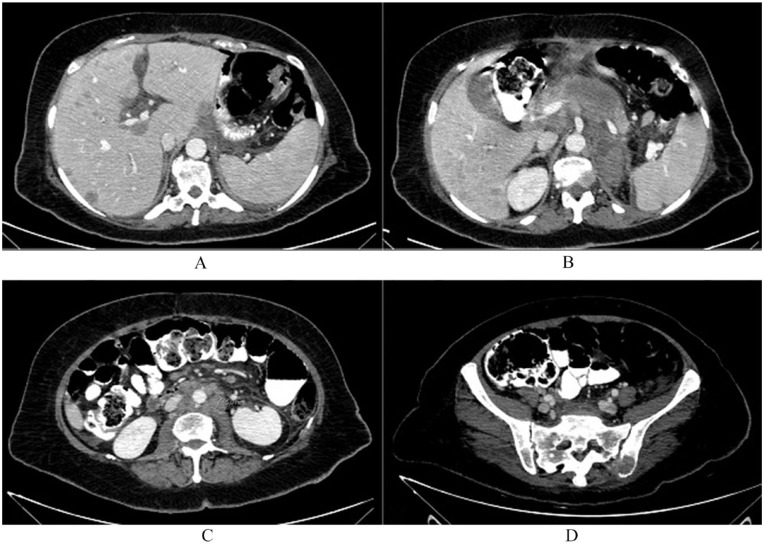

癌症相关性微血管病性溶血性贫血(CA-MAHA)是一种罕见的副肿瘤综合征。治疗 CA-MAHA 最有效的方法是解决潜在的恶性肿瘤问题。文献记载的 CA-MAHA 病例不足 50 例。在本文中,我们介绍了一名 51 岁的女性患者,她因胃腺癌并发 CA-MAHA 症状。尽管患者接受了胃癌新辅助化疗和辅助化疗,但病情仍出现进展,并在肝脏、胰腺和其他部位出现转移病灶。本报告强调了诊断 CA-MAHA 并将其与其他类似疾病(如弥散性血管内凝血(DIC)、溶血性尿毒症(HUS)、血栓性血小板减少性紫癜(TTP)和风湿性副肿瘤综合征)相鉴别所面临的挑战。此外,该研究还得出结论,CA-MAHA 预后不良,临床治疗效果有限,因此强调需要早期诊断和有效的管理策略。

Cancer-associated microangiopathic hemolytic anemia (CA-MAHA) is a rare paraneoplastic syndrome. The most effective approach to treating CA-MAHA is to address the underlying malignancy. Documented cases of CA-MAHA are limited to fewer than 50 patients in the literature. Herein, we present a 51-year-old female patient who developed CA-MAHA as a complication of gastric adenocarcinoma. Despite receiving neoadjuvant and adjuvant chemotherapy for gastric cancer, the patient experienced disease progression with metastatic lesions in the liver, pancreas, and other sites. This report highlights the challenges in diagnosing and distinguishing CA-MAHA from other similar conditions such as disseminated intravascular coagulation (DIC), hemolytic uremic syndrome (HUS), thrombotic thrombocytopenic purpura (TTP), and rheumatological paraneoplastic syndromes. Additionally, it concludes that CA-MAHA is associated with a poor prognosis and limited clinical benefit from treatment, emphasizing the need for early diagnosis and effective management strategies.